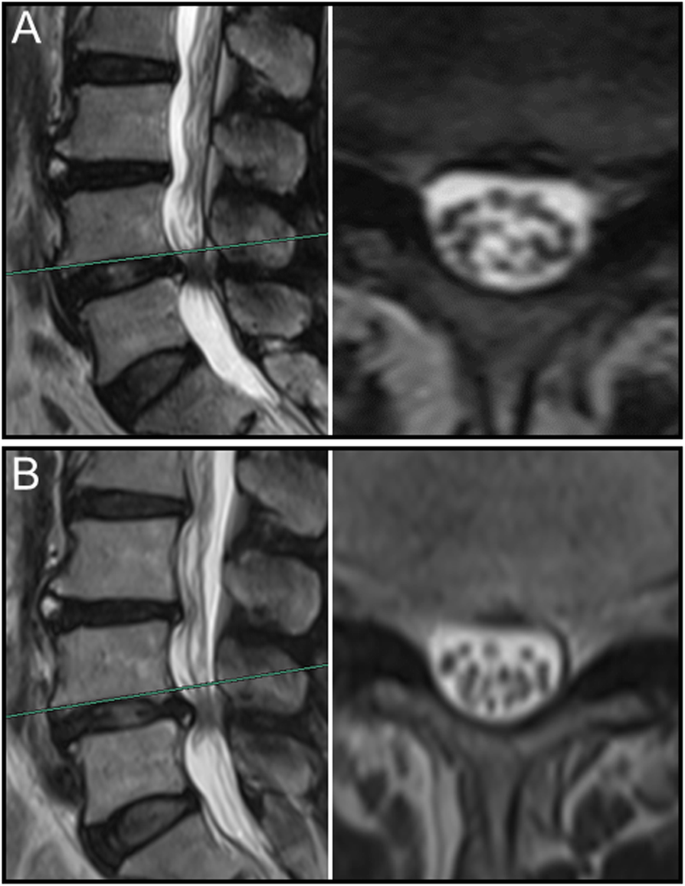

The sedimentation of nerve roots on MR images of various body position

Overall, nerve roots of 48 (85.7%) patients subsided to the ventral side of the dural sac on the prone MR images, although that of 8 (14.3%) patients remain stay in the dorsal side of dural sac. Of the 25 patients with a negative SedSign on supine MR images, the nerve roots settled to the ventral side of the dural sac on prone MR images in 24 patients (Fig. 1). Nerve roots in the remaining 1 patient, who was diagnosed as disc herniation, did not settle to the ventral dural sac (Fig. 2). For all the 31 patients with a positive SedSign, nerve roots subsided to the ventral side of the dural sac on the prone MR images in 24 patients (Table 2, Fig. 3). The nerve roots of the other 7 patients still stay (sequester) in the dorsal dural sac, which were due to single level (Fig. 4) or multiple level stenosis (Fig. 5). The nerve roots in patients with positive SedSign were more likely to stay in the dorsal dural sac on prone position MR images (22.6% vs 4%, P < 0.05, Table 2). In addition, the nerve roots subsided to the left dural sac in all the 5 patients when they were MR imaged on a left lateral position (Fig. 6).

It is of interest to explore spatial status of the nerve roots in the lumbar spinal canal in different body position and may provide implications for researches of spinal stenosis, since MR imaging is well able to observe the nerve roots due to its high resolution. As clearly demonstrated in the present study, gravity was the major factor determining the direction of nerve roots sedimentation. If the nerve roots do not subside along with the direction of gravity, a positive SedSign on supine MR images for example, there must be an integrated mechanical force (towards the ventral side) against the gravity so that the natural sedimentation of the nerve roots was restricted. Similarly, when changed to prone position, nerve roots of some patients did not settle down the ventral dural sac, and this phenomenon was more likely to occur in patients with disc herniation or spinal stenosis. Since positive nerve root SedSign in prone position was more likely presented in multi-level or severe LSS, it may be an indication of severity of LSS and suggestive of decompressions. Nevertheless, it requires large sample size research combined with the clinical data, such as walking distance and symptom duration.